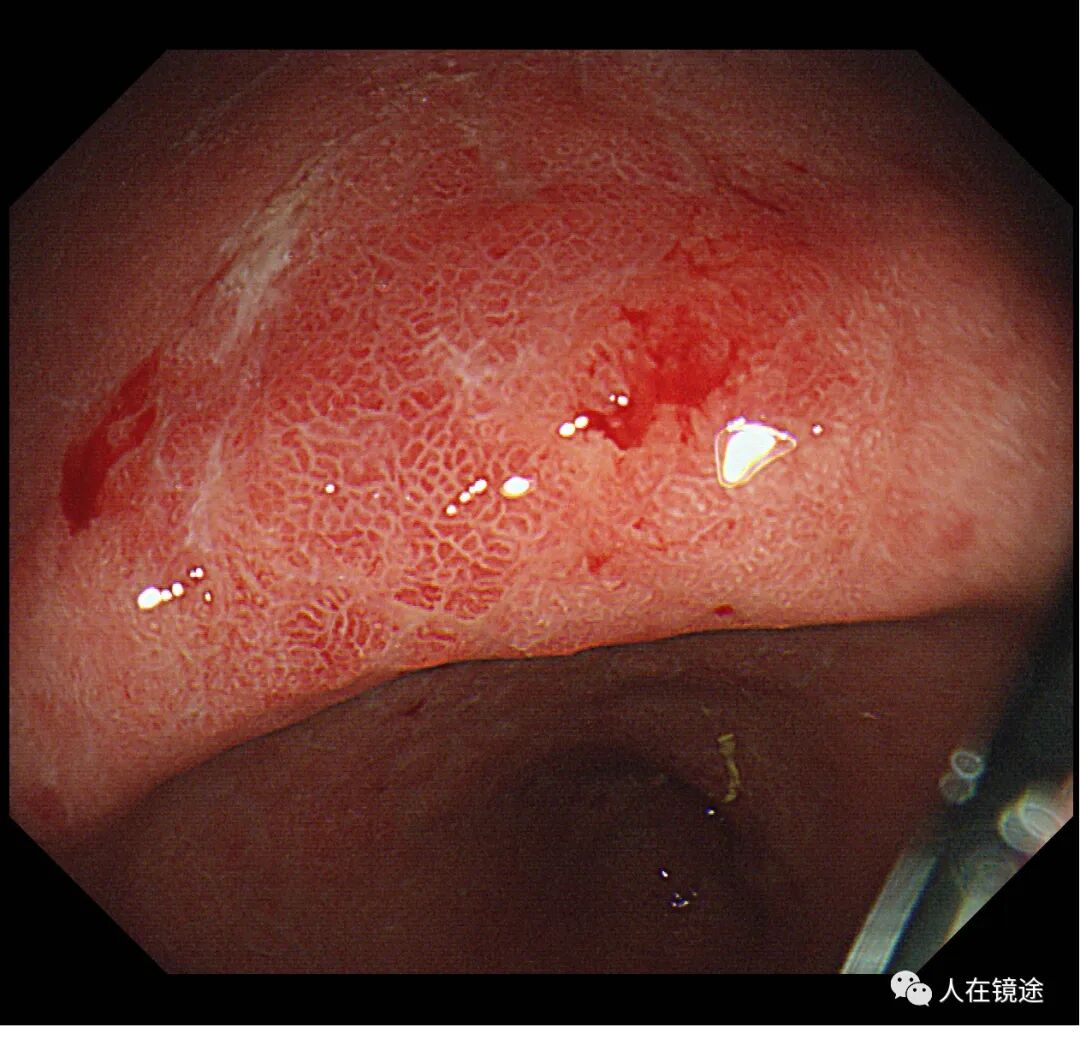

白光+近焦示:胃窦小弯见一0.8*1.2cmIIa粘膜发红病变,微结构稍紊乱,表面粘膜高低不平伴自发性出血。